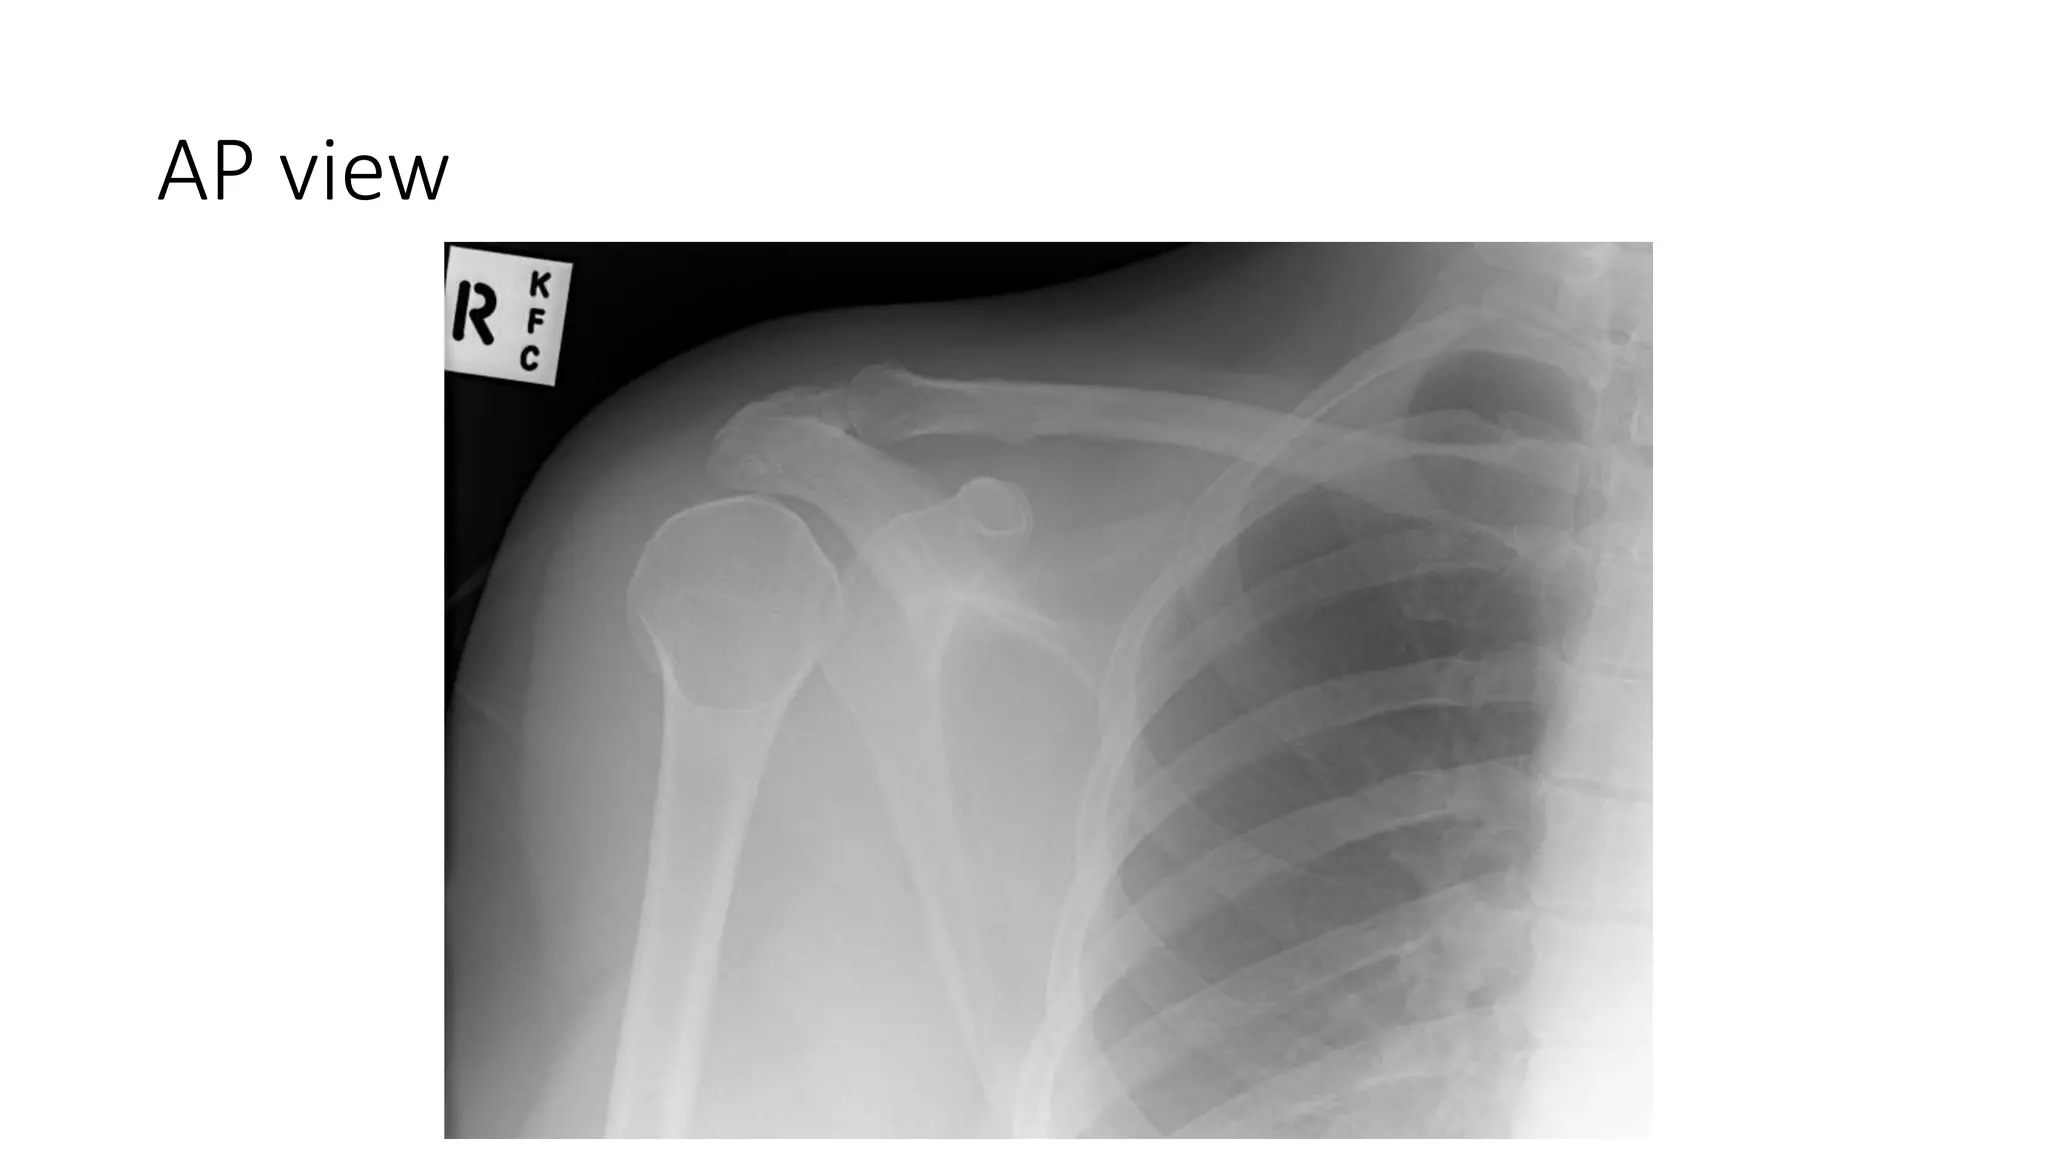

AP view

• AP :- unreliable and cannot be exclude posterior dislocation.

may show lightbulb sign.